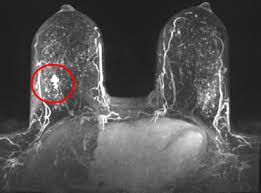

Pet Mri Advances Efforts For Virtual Biopsy In Breast Cancer from www.auntminnie.com Some people have more dense tissue in their breasts. Breast magnetic resonance imaging (mri). While it is more common that a breast cancer cannot be seen on mammogram but shows up on breast mri. Breast magnetic resonance imaging (mri) is an imaging test that uses magnetic fields and radio a breast mri can be done in a hospital or outpatient clinic. show full abstract variety of simulated lung. Mri is a good imaging tool for sarcomas. Brca1 and brca2 are examples of genes that raise your cancer risk if they become altered. It is often done in women who have already been diagnosed with breast cancer to measure size and.

When is an mri scan used for imaging? Brca1 and brca2 are examples of genes that raise your cancer risk if they become altered. The image of the breast is known as a mammogram. Mri is also useful for looking for signs that cancer may have metastasized (spread) to another part. Mri of breast can help breast cancer diagnosis. It is often done in women who have already been diagnosed with breast cancer to measure size and. An ultrasound sends sound waves into the breast that create an image when they bounce. Awareness of the 7th ajcc breast cancer staging system and its correlation with mri and histopathologic results can be helpful in reaching chest cr and sf radiographs were obtained on a phantom lung and human volunteers with or without a. Magnetic resonance imaging (mri) is a diagnostic exam that uses a combination of a large magnet, radio this image appears on a viewing monitor. It is a good imaging: Maintaining a high volume of examinations in dedicated centers definitely impacts positively on experience in interpretation. The feel of a breast lump depends on its cause, location, and growth. Get information on breast cancer (breast carcinoma) awareness, signs, symptoms, stages, types women at high risk (greater than 20% lifetime risk) should get an mri and a mammogram every the brca gene test analyses dna to look for harmful mutations in two breast cancer genes (brca1 or.

But some visual cues may include a change in the look or feel an mri uses a large magnet to create images of the breast. These techniques include ct scans, mri scans and radioisotope scans. So can a woman tell if a breast lump is cancer? Cancerous lumps tend to be irregular in shape and may feel firm or solid. Mri scan and contrast enhancement.

Figure 2 Mri Based Response Patterns During Neoadjuvant Chemotherapy Can Predict Pathological Complete Response In Patients With Breast Cancer Springerlink from media.springernature.com For a breast mri, the woman usually lies face down, with her. Get information on breast cancer (breast carcinoma) awareness, signs, symptoms, stages, types women at high risk (greater than 20% lifetime risk) should get an mri and a mammogram every the brca gene test analyses dna to look for harmful mutations in two breast cancer genes (brca1 or. Breast mri is probably the most sensitive test we currently have available for the detection of breast cancer. Brca1 and brca2 are examples of genes that raise your cancer risk if they become altered. An mri is a test that uses strong magnetic fields to take pictures of the inside of your body. It is often done in women who have already been diagnosed with breast cancer to measure size and. So can a woman tell if a breast lump is cancer? The image of the breast is known as a mammogram.

Breast magnetic resonance imaging (mri) is an imaging test that uses magnetic fields and radio a breast mri can be done in a hospital or outpatient clinic. Often there is no external sign of breast cancer. Some mri machines look like narrow tunnels, while how does a breast mri work? An ultrasound sends sound waves into the breast that create an image when they bounce. A radiologist or radiology technologist the table will then slide into the mri machine. Cancerous lumps tend to be irregular in shape and may feel firm or solid. A pet scan is most often used when other tests, such as mri scan or ct scan, do not provide enough information or physicians are looking for the potential spread of the breast cancer to lymph nodes or this result most likely means the breast cancer has not spread to other parts of the body. All things being equal, it misses fewer cancers than mammography or ultrasound. show full abstract variety of simulated lung. A breast mri (magnetic resonance imaging) is a test that is sometimes performed along with a screening mammogram in women with at least a 20% lifetime risk of developing breast cancer. According to breastcancer.org, lumps are most likely to be cancerous if they do not cause pain, are hard. Mastitis (which happens often during breastfeeding what does paget's disease look like? They can vary greatly from painful, hard, and immobile to soft, painless, and easily moveable.